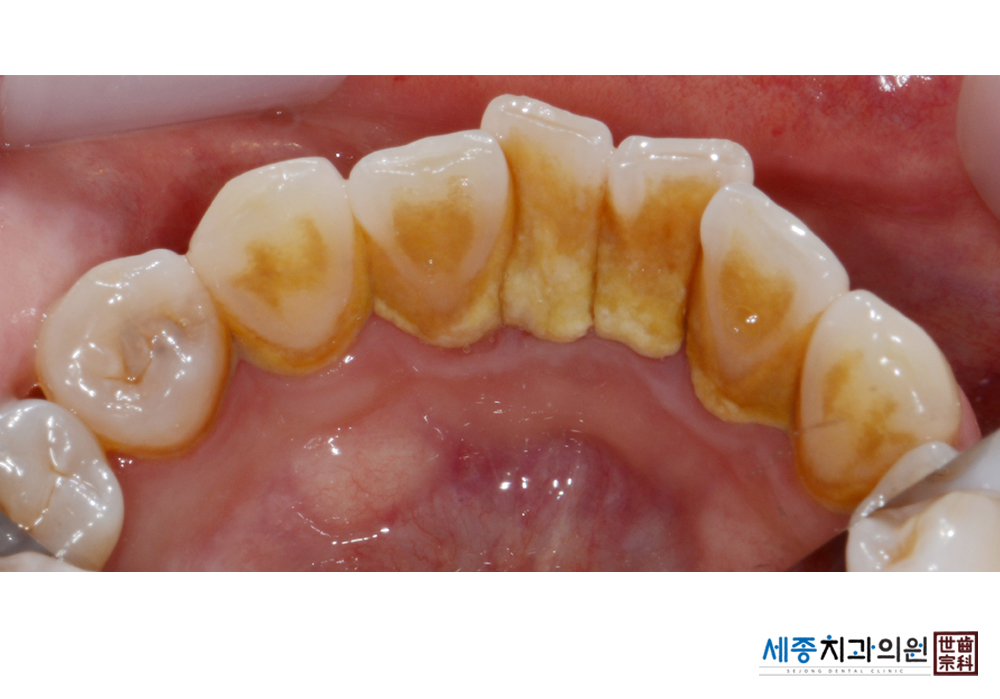

[스케일링] 치주질환 예방 스케일링

치료전 : 2022-05-25

치료후 : 2022-05-25

가글마취&저주파 스켈러를 사용한 스케일링